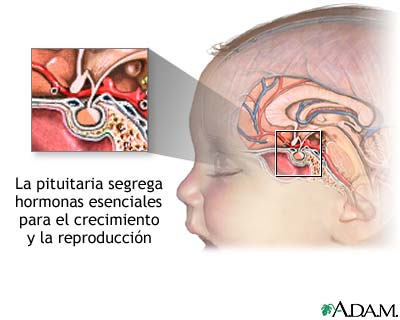

Figura 1: la glándula pituitaria ó hipófisis. Imagen recuperada de http://www.nlm.nih.gov/medlineplus/spanish/ency/esp_imagepages/17227.htm, el 17 de julio de 2007

Hoy, vamos a agregar un ingrediente más, en este peculiar programa de cocina cerebral, una estructura similar a un guisante (algunos científicos hablan del formato de pera muy pequeña ó de San Juan), con un peso de 0.5 gramos, que se denomina científicamente glándula pituitaria (también conocida como hipófisis, “crecimiento inferior”) y que se aloja en un espacio óseo, la silla turca, del hueso esfenoides, situada en la base del cráneo, en la fosa cerebral media, que conecta con el hipotálamo a través del tallo pituitario o tallo hipofisario. La etimología es sumamente curiosa para comprender anatómicamente esta microestructura de extraordinaria importancia en las mujeres y hombres, por este orden. Pituitaria significa que contiene o segrega pituita, del latín “pituita”: secreción, fluido, moco, flema, formando parte de la medicina tradicional junto a los tres “humores” restantes: sangre, bilis amarilla y bilis negra. Es una superestructura del sistema endocrino dado que ejerce un control férreo sobre ocho glándulas endocrinas que explicamos a continuación.